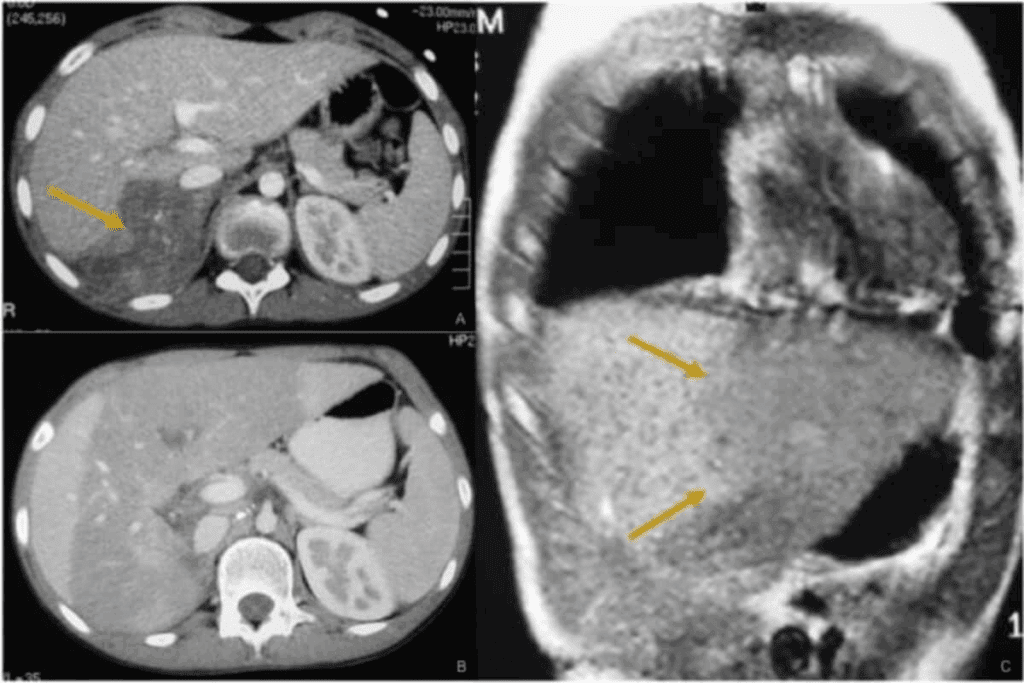

Advanced Imaging Techniques for Neuroblastoma

Diagnosing and staging neuroblastoma rely on advanced imaging. These techniques give vital info on the tumor’s size and spread. This info is key for choosing the right treatment.

CT Scans and MRI

Computed Tomography (CT) scans and Magnetic Resonance Imaging (MRI) are key for diagnosing neuroblastoma. CT scans show detailed cross-sections, helping spot the tumor’s size and its position. MRI offers great contrast for soft tissues, helping see how far the tumor has spread.